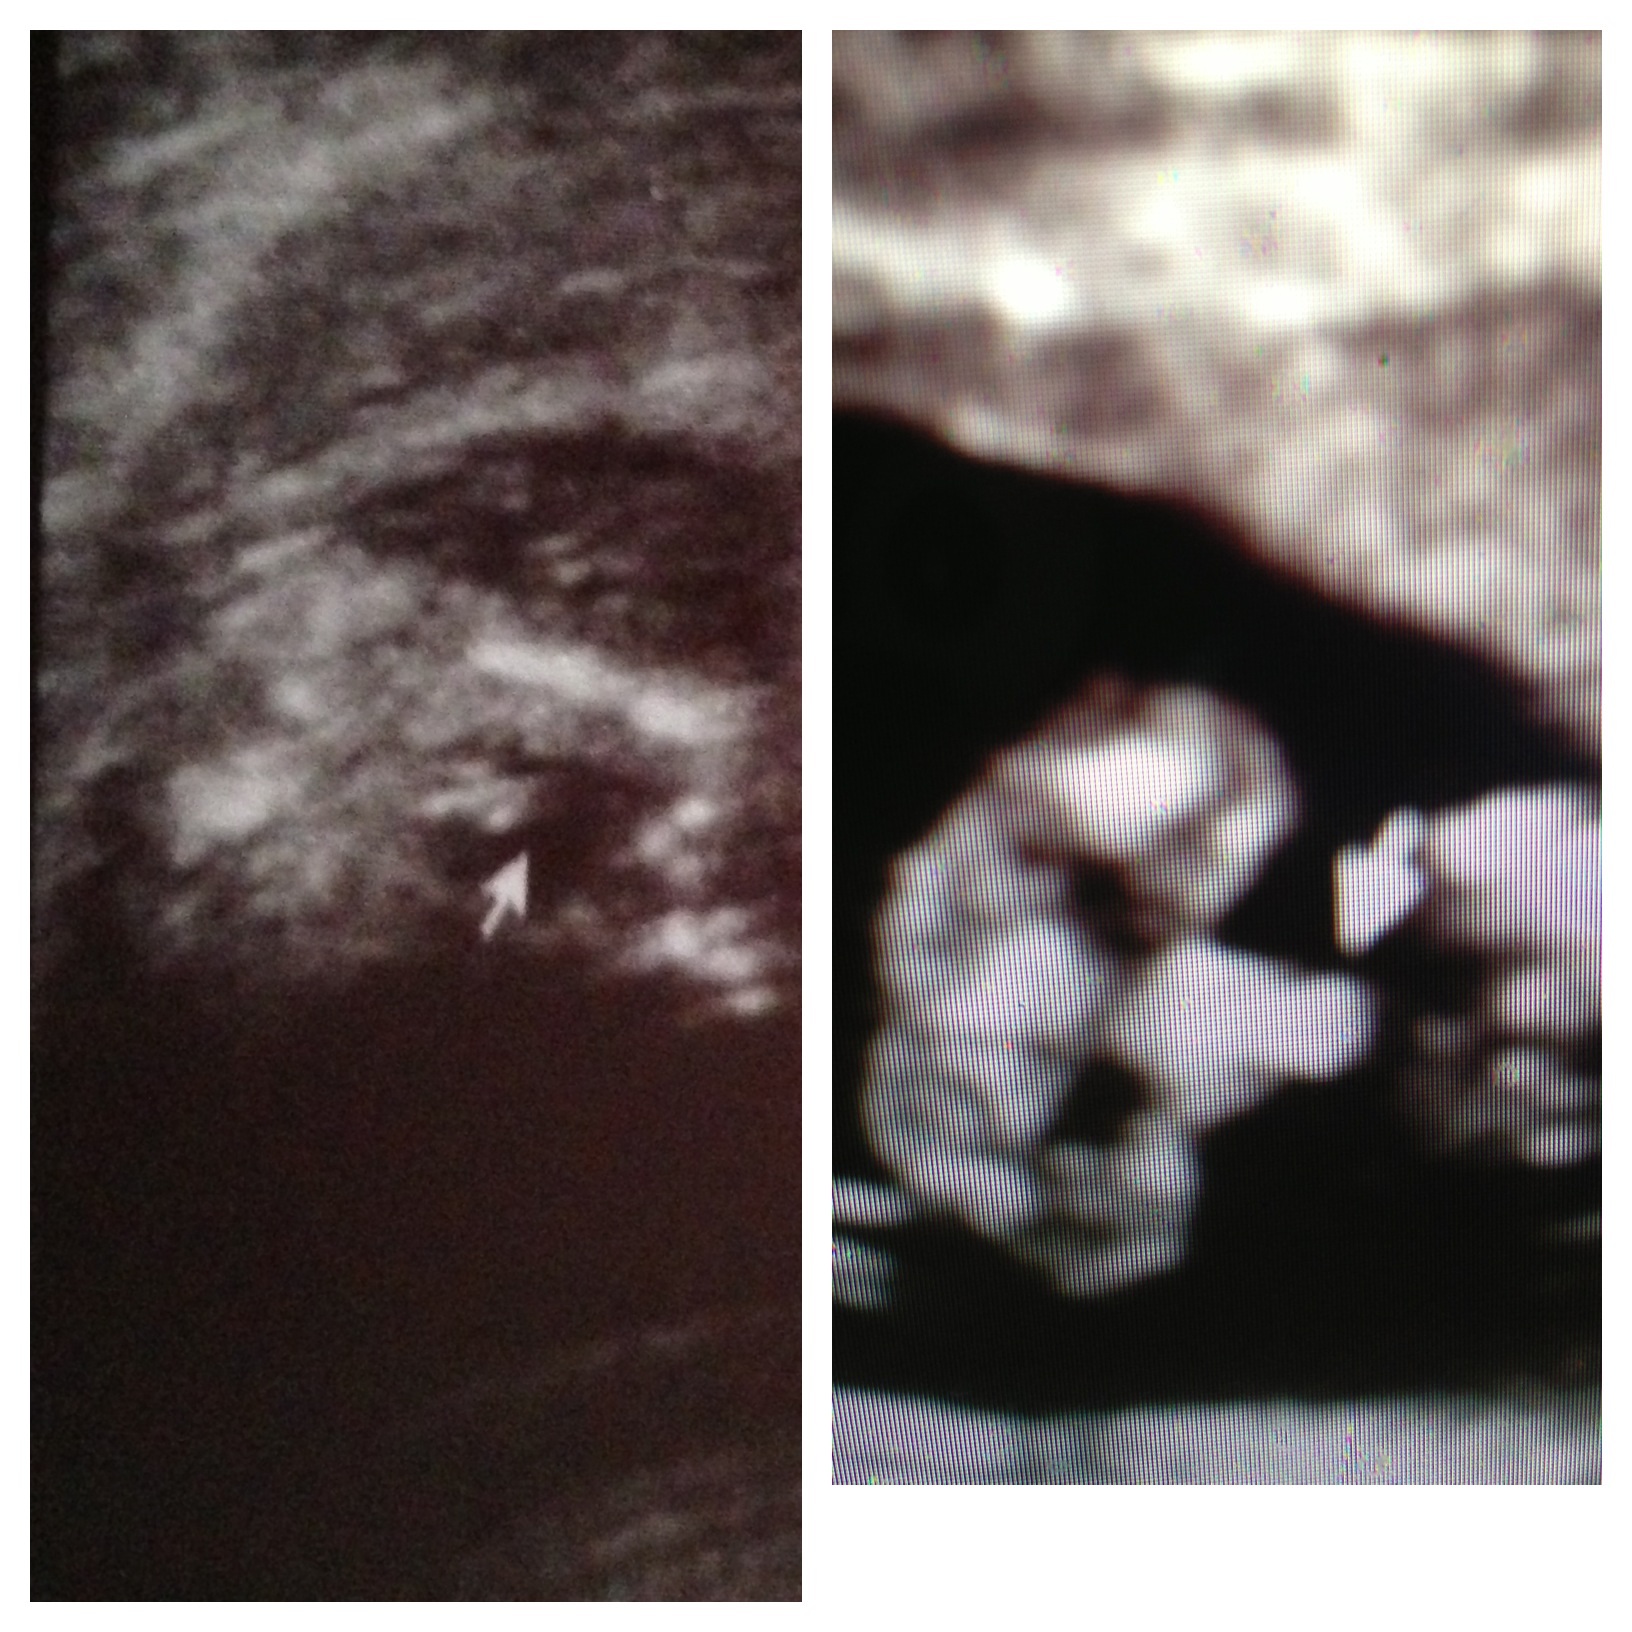

Told boy at 13wk 5 days. Please help confirm. TIA

Hey, ladies! Thanks so much for opening and reading. As the title says , I was told to expect a boy at 13 weeks and 5 days. I went to a 4d ultrasound place that says they can determine at 14 weeks. Anyway, I didn't see the goods myself too much. But she printed out pics of what she said were "perfect boy parts."

I got home and looked at the pics and compared to my

Other ds's 14 week 5 day scan (pictured on right)... And here it

Is.

I know a week is a big difference and all babies are different.... But is the one on the left for sure a boy? I know anything this early is a dumb idea to do potty shots. But i wasnt thinking clearly. Anyway, What's your thoughts. Thank you so much!Attachment 13851